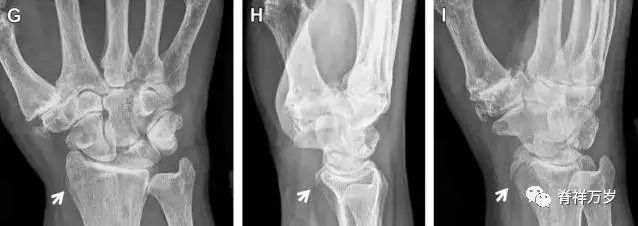

腕掌关节骨折脱位为高能量损伤,常伴有神经损伤。腕掌关节组成骨多,侧位片上重叠遮挡多,骨折不易发现,容易漏诊。在前后位片上,关节面不平滑、关节间隙不对称、关节皮质破坏、关节面重叠常提示腕掌关节骨折脱位。特别是第 4、5 腕掌关节脱位,在前后位片上不容易发现;该损伤不稳定,也称为「变异型拳击手损伤/骨折」。

图 4 第 4、5 腕掌关节骨折脱位。(A)正常腕掌关节,关节面平衡起伏、平行;前后位(B)、斜位(C)、侧位(D),第 5 掌骨近端附近软组织肿胀(白色箭头),冠状面关节面重叠,背侧撞击剪切应力致钩状骨骨折(*),在前后位及斜位片上可见双密度影。第 4 掌骨底部可见微小骨折碎片(D,虚线箭头),第 4、5 掌骨掌侧成角。(E~G)变异型拳击手损伤:第 4、5 掌骨背侧脱位而未见骨折(E,虚线方框),钩状骨有骨折小碎片(F,短虚线箭头),第 4 掌骨基底部关节内骨折(G,长虚线箭头)。